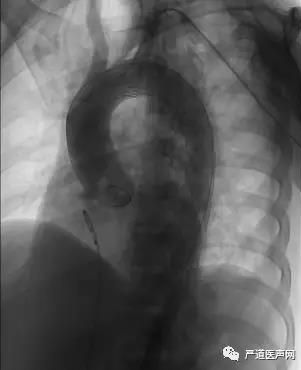

支架完全释放

复查造影示支架贴壁良好,未见造影剂渗漏。

支架释放后复查造影提示无内漏,弓上分支动脉血流通畅。